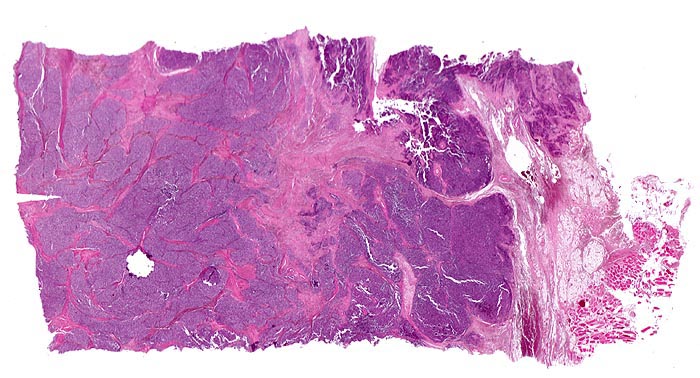

Ewing-Sarkom

Weichteile Bein

Lobulierter Tumor bestehend aus zelldichten soliden Tumorplatten umgeben von Bindegewebssepten. Die Begrenzung ist scharf. In unmittelbarer Nachbarschaft des Tumors sind Fettgewebe und Skelettmuskulatur erkennbar.

Femuramputat mit festem grauweissem intraossärem feucht-glänzendem Tumorgewebe. Die extraossäre Weichteilkomponente ist weicher und brüchiger. Der Gewebsschnitt stammt aus der extraossären Weichteilkomponente.

Zunehmende Schmerzen im rechten Oberschenkel mit Weichteilschwellung- und Erwärmung seit mehreren Monaten. Keine Traumaanamnese. Klinisch wird zunächst eine Osteomyelitis vermutet. Aufgrund der Röntgenaufnahme, welche neben einer Weichteilmasse eine schlecht begrenzte, lytische Läsion in der Diaphyse des Femurs mit zwiebelschalenförmiger Periostreaktion zeigt, wird ein maligner Knochentumor diagnostiziert.

Histologie

Scan